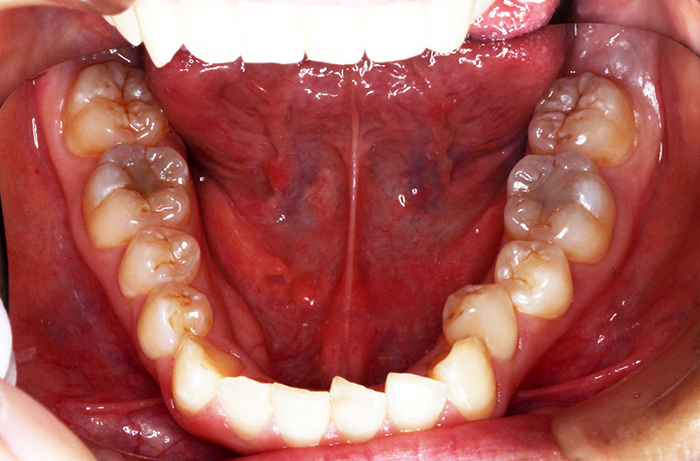

治療前

before

患者の症状 上顎前歯の前突、八重歯

治療方法 上下左右の第一小臼歯抜歯で、マウスピース型カスタムメイド矯正歯科装置による矯正

治療結果 上顎前歯の前突、八重歯が改善されました。

その他治療に関する情報

歯並びをより良くするために追加でアライナーを発注しました。